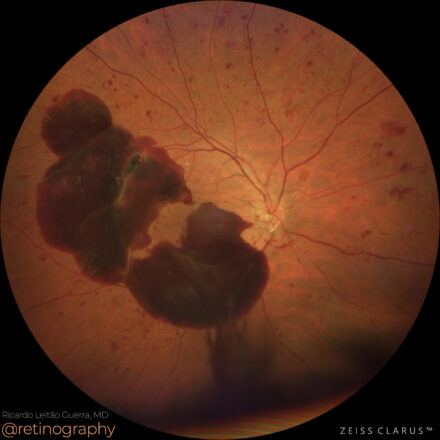

Proliferative Diabetic Retinopathy

38yo

38yo In proliferative diabetic retinopathy (PDR), subhyaloid hemorrhage results from fragile neovascularization bleeding into the preretinal space. The green channel enhances contrast, improving hemorrhage visualization on fundus imaging. Optical Coherence Tomography (OCT) shows a well-demarcated, hyperreflective hemorrhagic pocket between the retina and the posterior hyaloid face, which can affect visual acuity […]